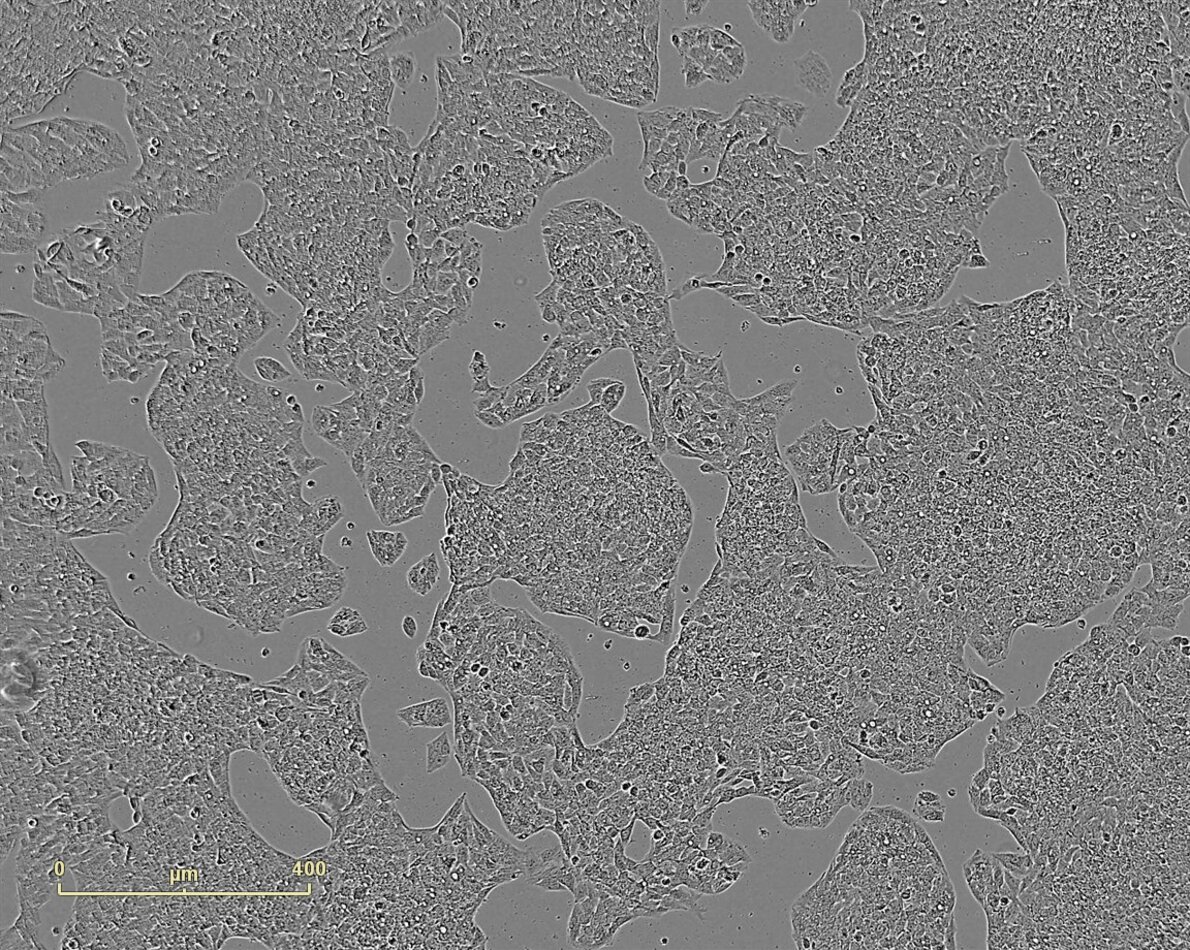

Several cell lines are available at PCBIS for the study of cytotoxicity.